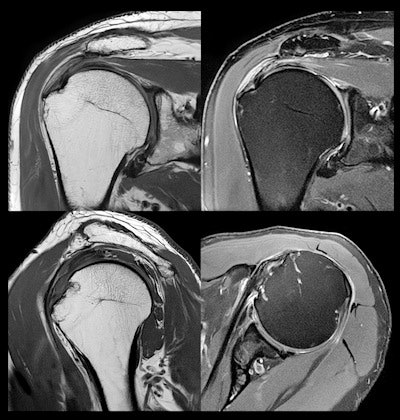

The new applications run from the prostate to the shoulders, including all joints and the heart, pelvis, abdomen, and spine. What's more, AiCE DLR can be combined with accelerated scanning technologies, such Canon's compressed Speeder technique, which received 510(k) clearance earlier this year.

MR images of the shoulder acquired at 3-tesla and reconstructed with AiCE show submillimeter resolution for detailed orthopedic imaging.Finally, Canon is discussing the results of what it calls the AiCE Challenge, an experiment in which blinded observers compared conventional 3-tesla MR images with 1.5-tesla images reconstructed with AiCE and were asked to tell the two apart. The company said that radiologists got the correct answer only 50% of the time, indicating the equivalence of AiCE-reconstructed 1.5-tesla images to the 3-tesla gold standard.